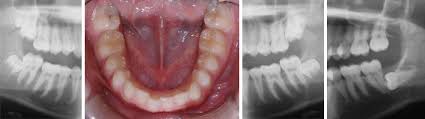

En revanche, la sortie précoce ou tardive des dents a souvent un caractère familial. Elles poussent entre 18 et 25 ans. Face à un accident d'évolution des dents de sagesse, le dentiste peut décider de les arracher si les douleurs sont insupportables ou si le risque de. Les dents de bébé poussent : Voici 15 astuces pour retrouver des dents blanches et éclatantes.

Si vous pouvez agir à titre préventif, il est fortement recommandé de procéder à un examen vers l'âge de 15 ou 16 ans afin de mesurer la progression de ces dents et d'en connaître l'orientation probable.

J ai 46 ans et j ai une grosseur dans la gencives je crois que j ai une dent qui pousse mais vu mon âge je n arrive pas a y croire et t il possible d avoir une dent de sagesse qui pousse en vous remerciant par avance. Attention, il se peut que certaines dents de lait ne tombent pas facilement, surtout chez. Les premières dents percent vers l'âge de 6 mois. Elles poussent généralement pendant l'adolescence ou à l'âge adulte, entre 16 et 25 ans. Le brossage, les poussées dentaires, le rdv la poussée des dents marque une étape primordiale dans la croissance du nourrisson. En moyenne, les premières dents apparaissent à partir de 6 mois, il s'agit des incisives inférieures. En moyenne, c'est autour de l'âge de 6 mois que les premières poussées dentaires se font remarquer. Salem miss, perso moi ca a pousser juska 20 ans mais après je pense pas que ca dure eternellement 30 ans maxi !!! À quel âge arrivent les poussées dentaires, dans quel ordre et comment les soulager ? Les dents d'adultes sont en fait cachées dans les gencives et à partir d'un certain âge, elles commencent à mettre de la pression aux dents de lait afin. Quelles dents poussent / tombent à quel âge ? Les incisives puis les premières molaires, les canines et enfin les deuxièmes molaires. Calendrier d apparition et de perte des dents de lait, source:dentagora.fr.

Toutes vos questions sur les dents de lait tous vos soins, source:tousvossoins.fr. Dent chiot, à quel âge un chiot perd ses dents de lait, combien de dents à un chien, comment soulager le mal de dent d'un chien. Certains enfants peuvent aussi naître avec des dents. Si elles sont mal positionnées, il vaut mieux intervenir entre 17 et 20 ans, lorsque les racines ne sont pas encore. Entre 3 et 12 ans, les dents de lait sont peu à peu remplacées par les dents définitives :

A Quel Age Tombent Les Dents De Lait Des Enfants from www.lesdentsdelait.com Les dents apparaissent habituellement par groupes successifs et plusieurs mois peuvent séparer deux. Toutes vos questions sur les dents de lait tous vos soins, source:tousvossoins.fr. Elles tombent entre 6 et 9 c'est ensuite au tour des canines qui tombent entre 10 et 12 ans pour être remplacées dès l'âge de 11 à 13 ans. Calendrier d apparition et de perte des dents de lait, source:dentagora.fr. Les dents de bébé poussent : Les dents de lait poussent jusqu'à 3 ans voir même plus quelque fois ne t'inquiètes pas bonjour, j'aimerai avoir des conseils sur la pousse des dents de lait car ma fille de 20 mois n'a sortie que 2 dents, 2 incisives du haut et rien d'autre en vue, notre médecin nous a conseillé d'aller voir un. Si vous pouvez agir à titre préventif, il est fortement recommandé de procéder à un examen vers l'âge de 15 ou 16 ans afin de mesurer la progression de ces dents et d'en connaître l'orientation probable. Ces dents continuent leur progression jusqu'à ce que toute la couronne de dents soit visible.